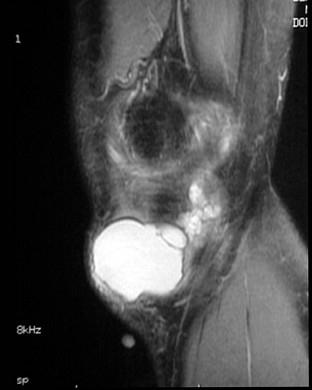

问题 男,21岁,膝关节疼痛,行走困难,曾有外伤史,请结合所提供的图像,选择最佳选项 ( )

选项 A、未见异常 B、前十字韧带撕裂与巨大半月板囊肿 C、内侧半月板撕裂 D、巨大半月板囊肿 E、内侧半月板撕裂与巨大半月板囊肿

答案 E